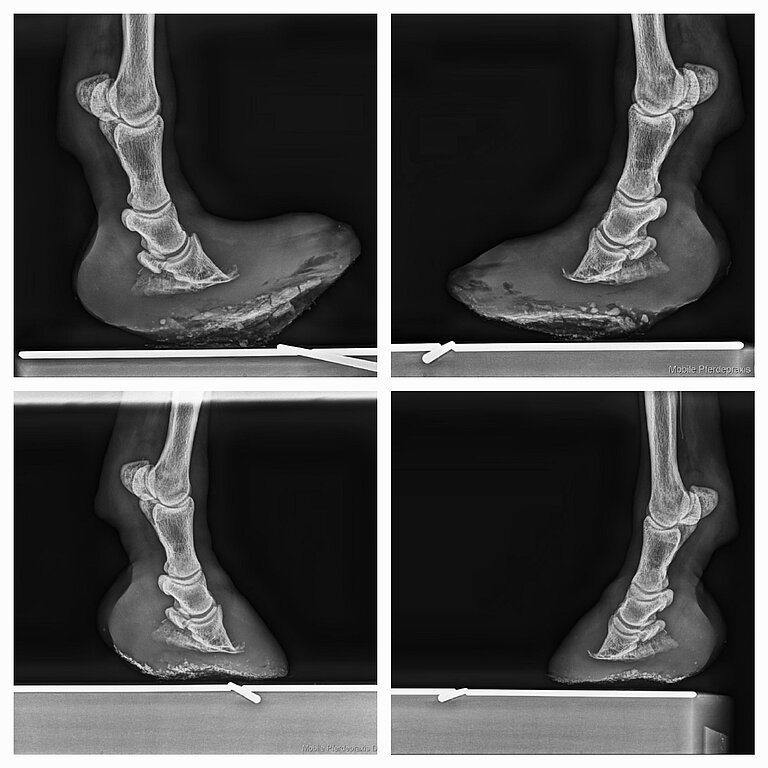

Oft sind die Ursache der orthopädischen Probleme, wegen der die Pferde bei mir vorstellig werden, mit Fehlern “im Fundament” (Hufe) verbunden oder es gab pathologische Veränderungen aufgrund bestimmter Erkrankungen. Mit einer angepassten Hufbearbeitung und eines individuellen Beschlags können diese Probleme deutlich verbessert oder beseitigt werden..

Gerne arbeite ich mit Hufschmieden und Hufbearbeitern zusammen und berate individuell. Zudem führe ich bei gravierenden bzw. komplizierten Fällen (z.B. bei Hufrehe) auch selbst Hufbearbeitungen durch und passe einen Alternativbeschlag, Klebebeschlag oder auch Castverbände an. Je nach Bedarf wähle ich das passende Material (Duplos, Goodsmith-Platten, Glu-Shu, o.ä.) aus.